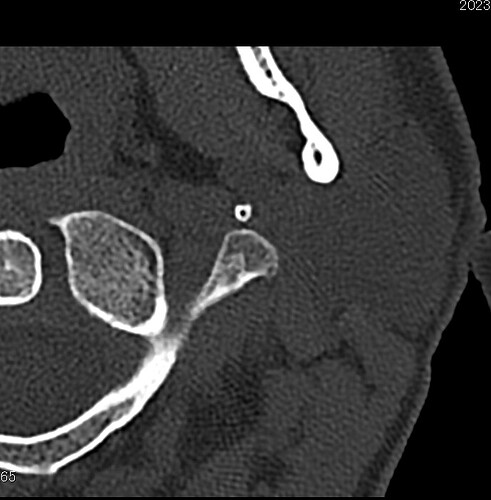

I do have plain CT of head/sinus bones a CTM of cervical spine that just covers TB area, and two CTA/Vs. Is CT of temporal bone a whole other specific scan? If so, I mean… I should already be a freaking glow stick, so what’s one more?